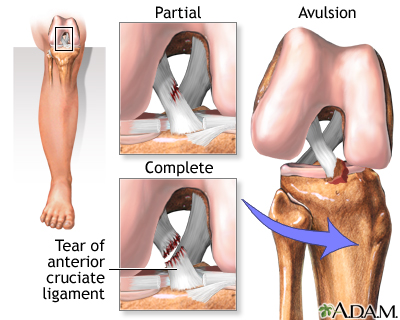

An anterior cruciate ligament injury is the over-stretching or tearing of the anterior cruciate ligament (ACL) in the knee. A tear may be partial or complete.

Most ACL tears occur in the middle of the ligament, or the ligament is pulled off the thigh bone. These injuries form a gap between the torn edges, and do not heal on their own.